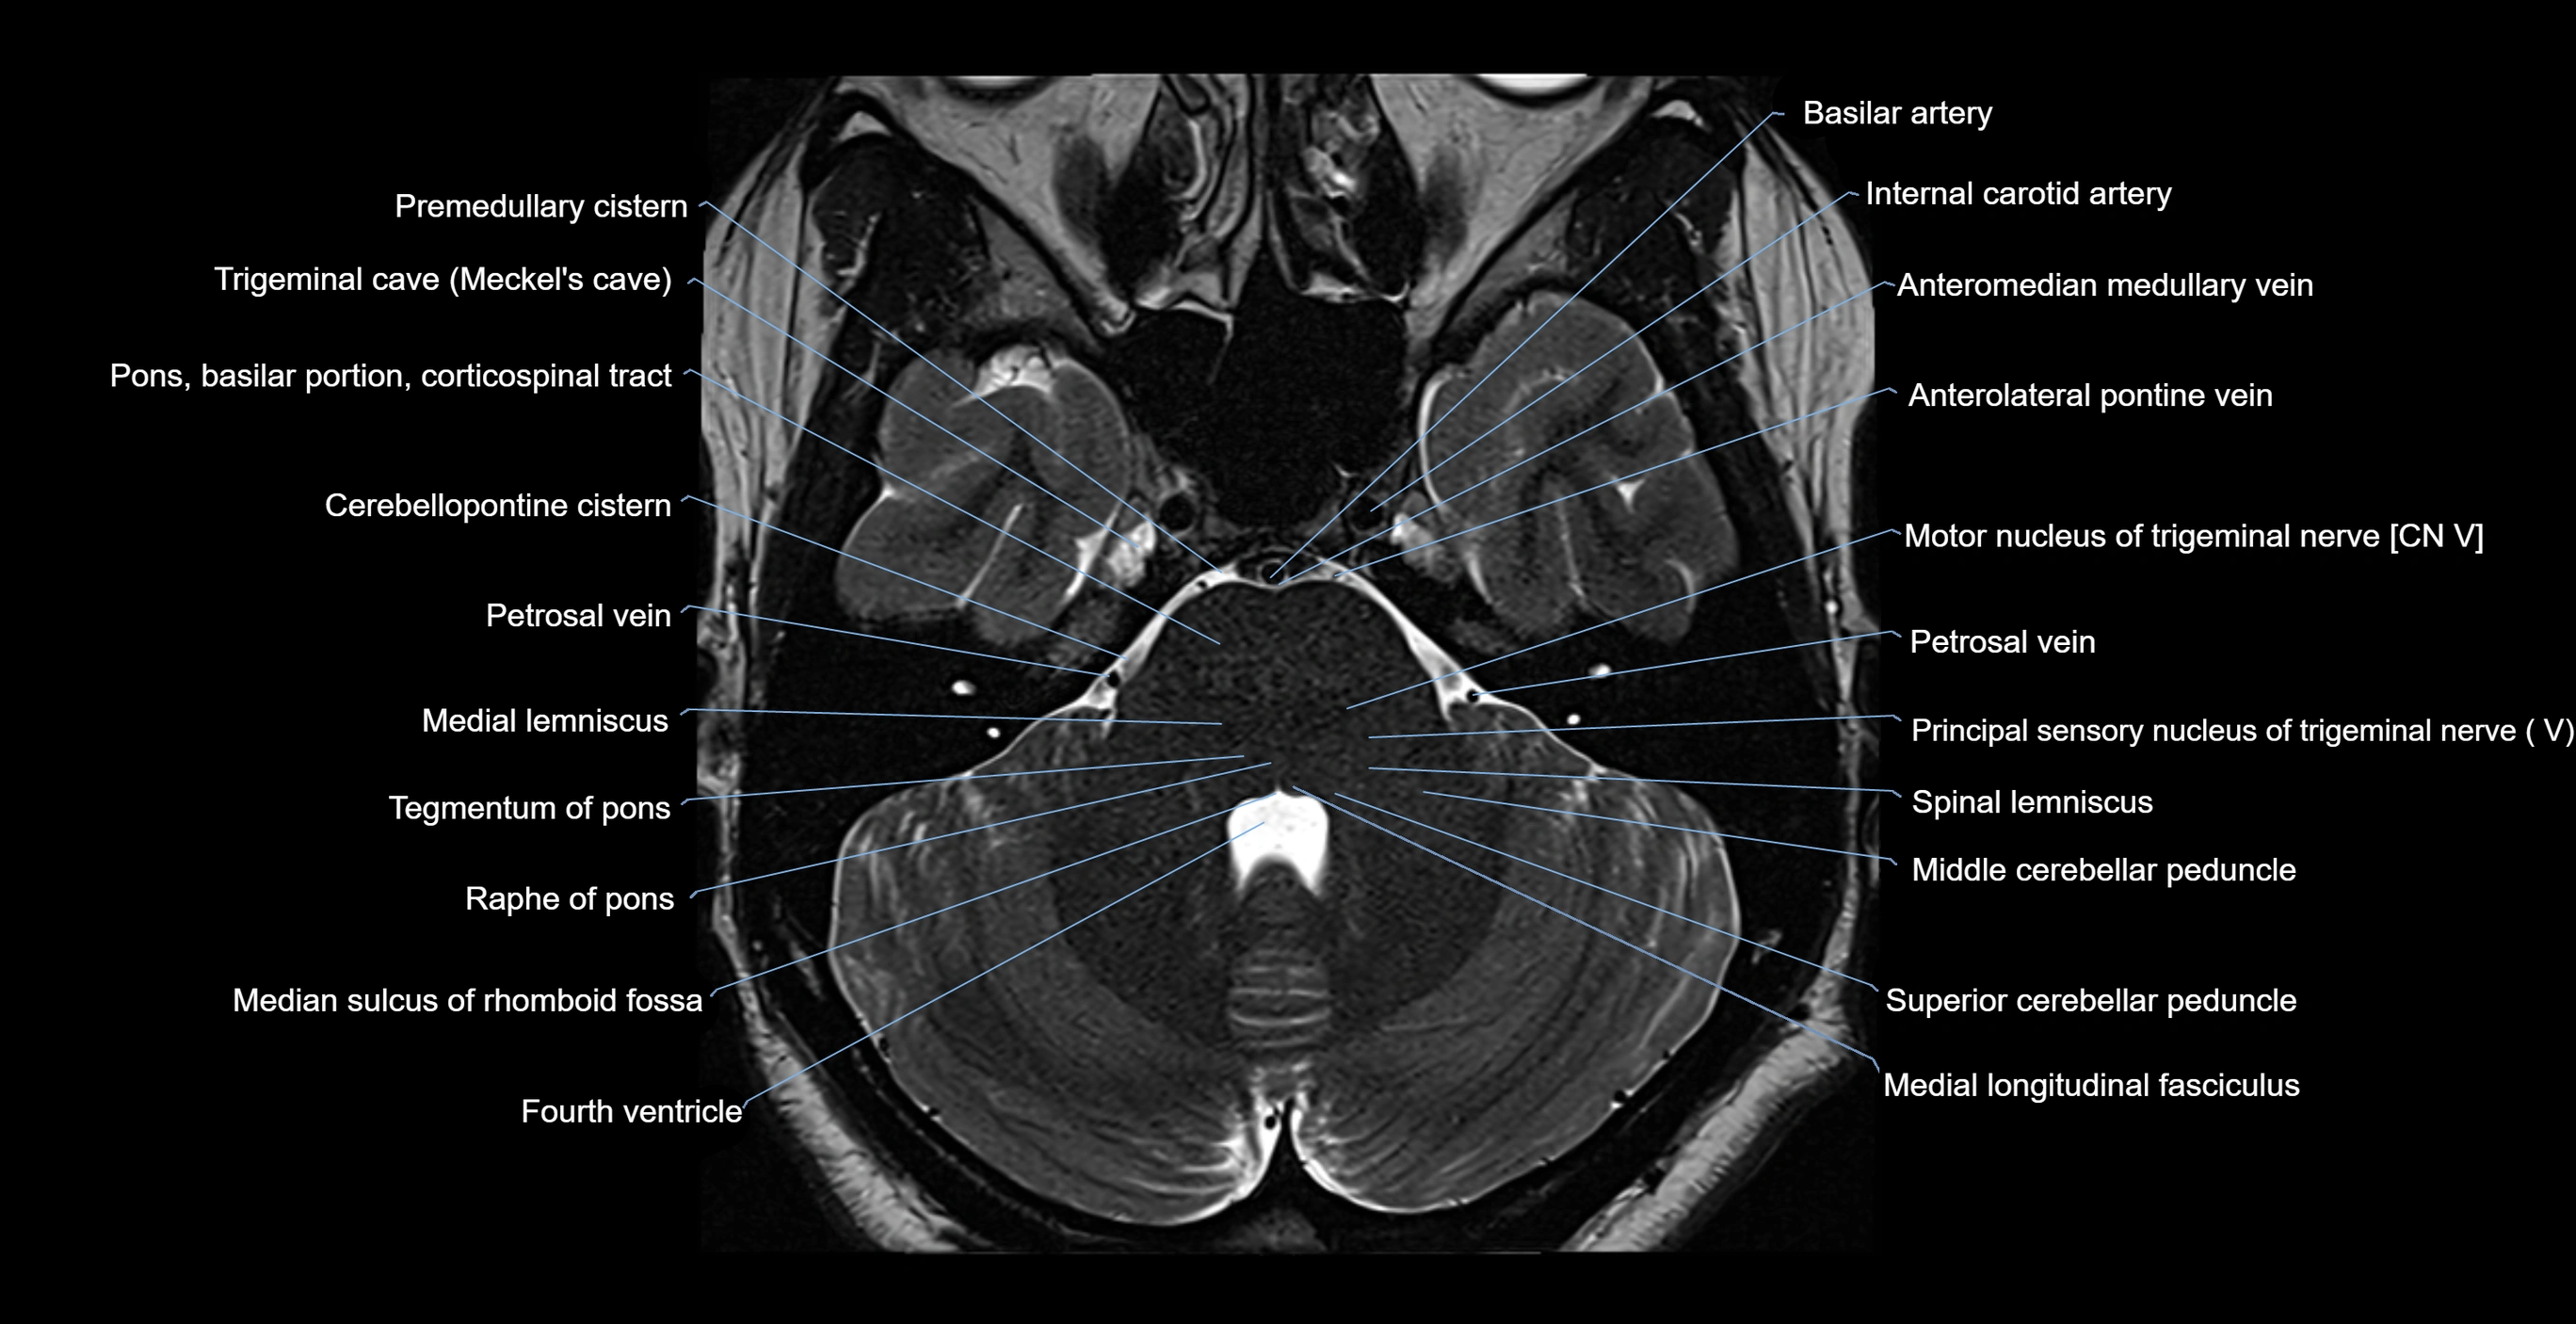

MRI images